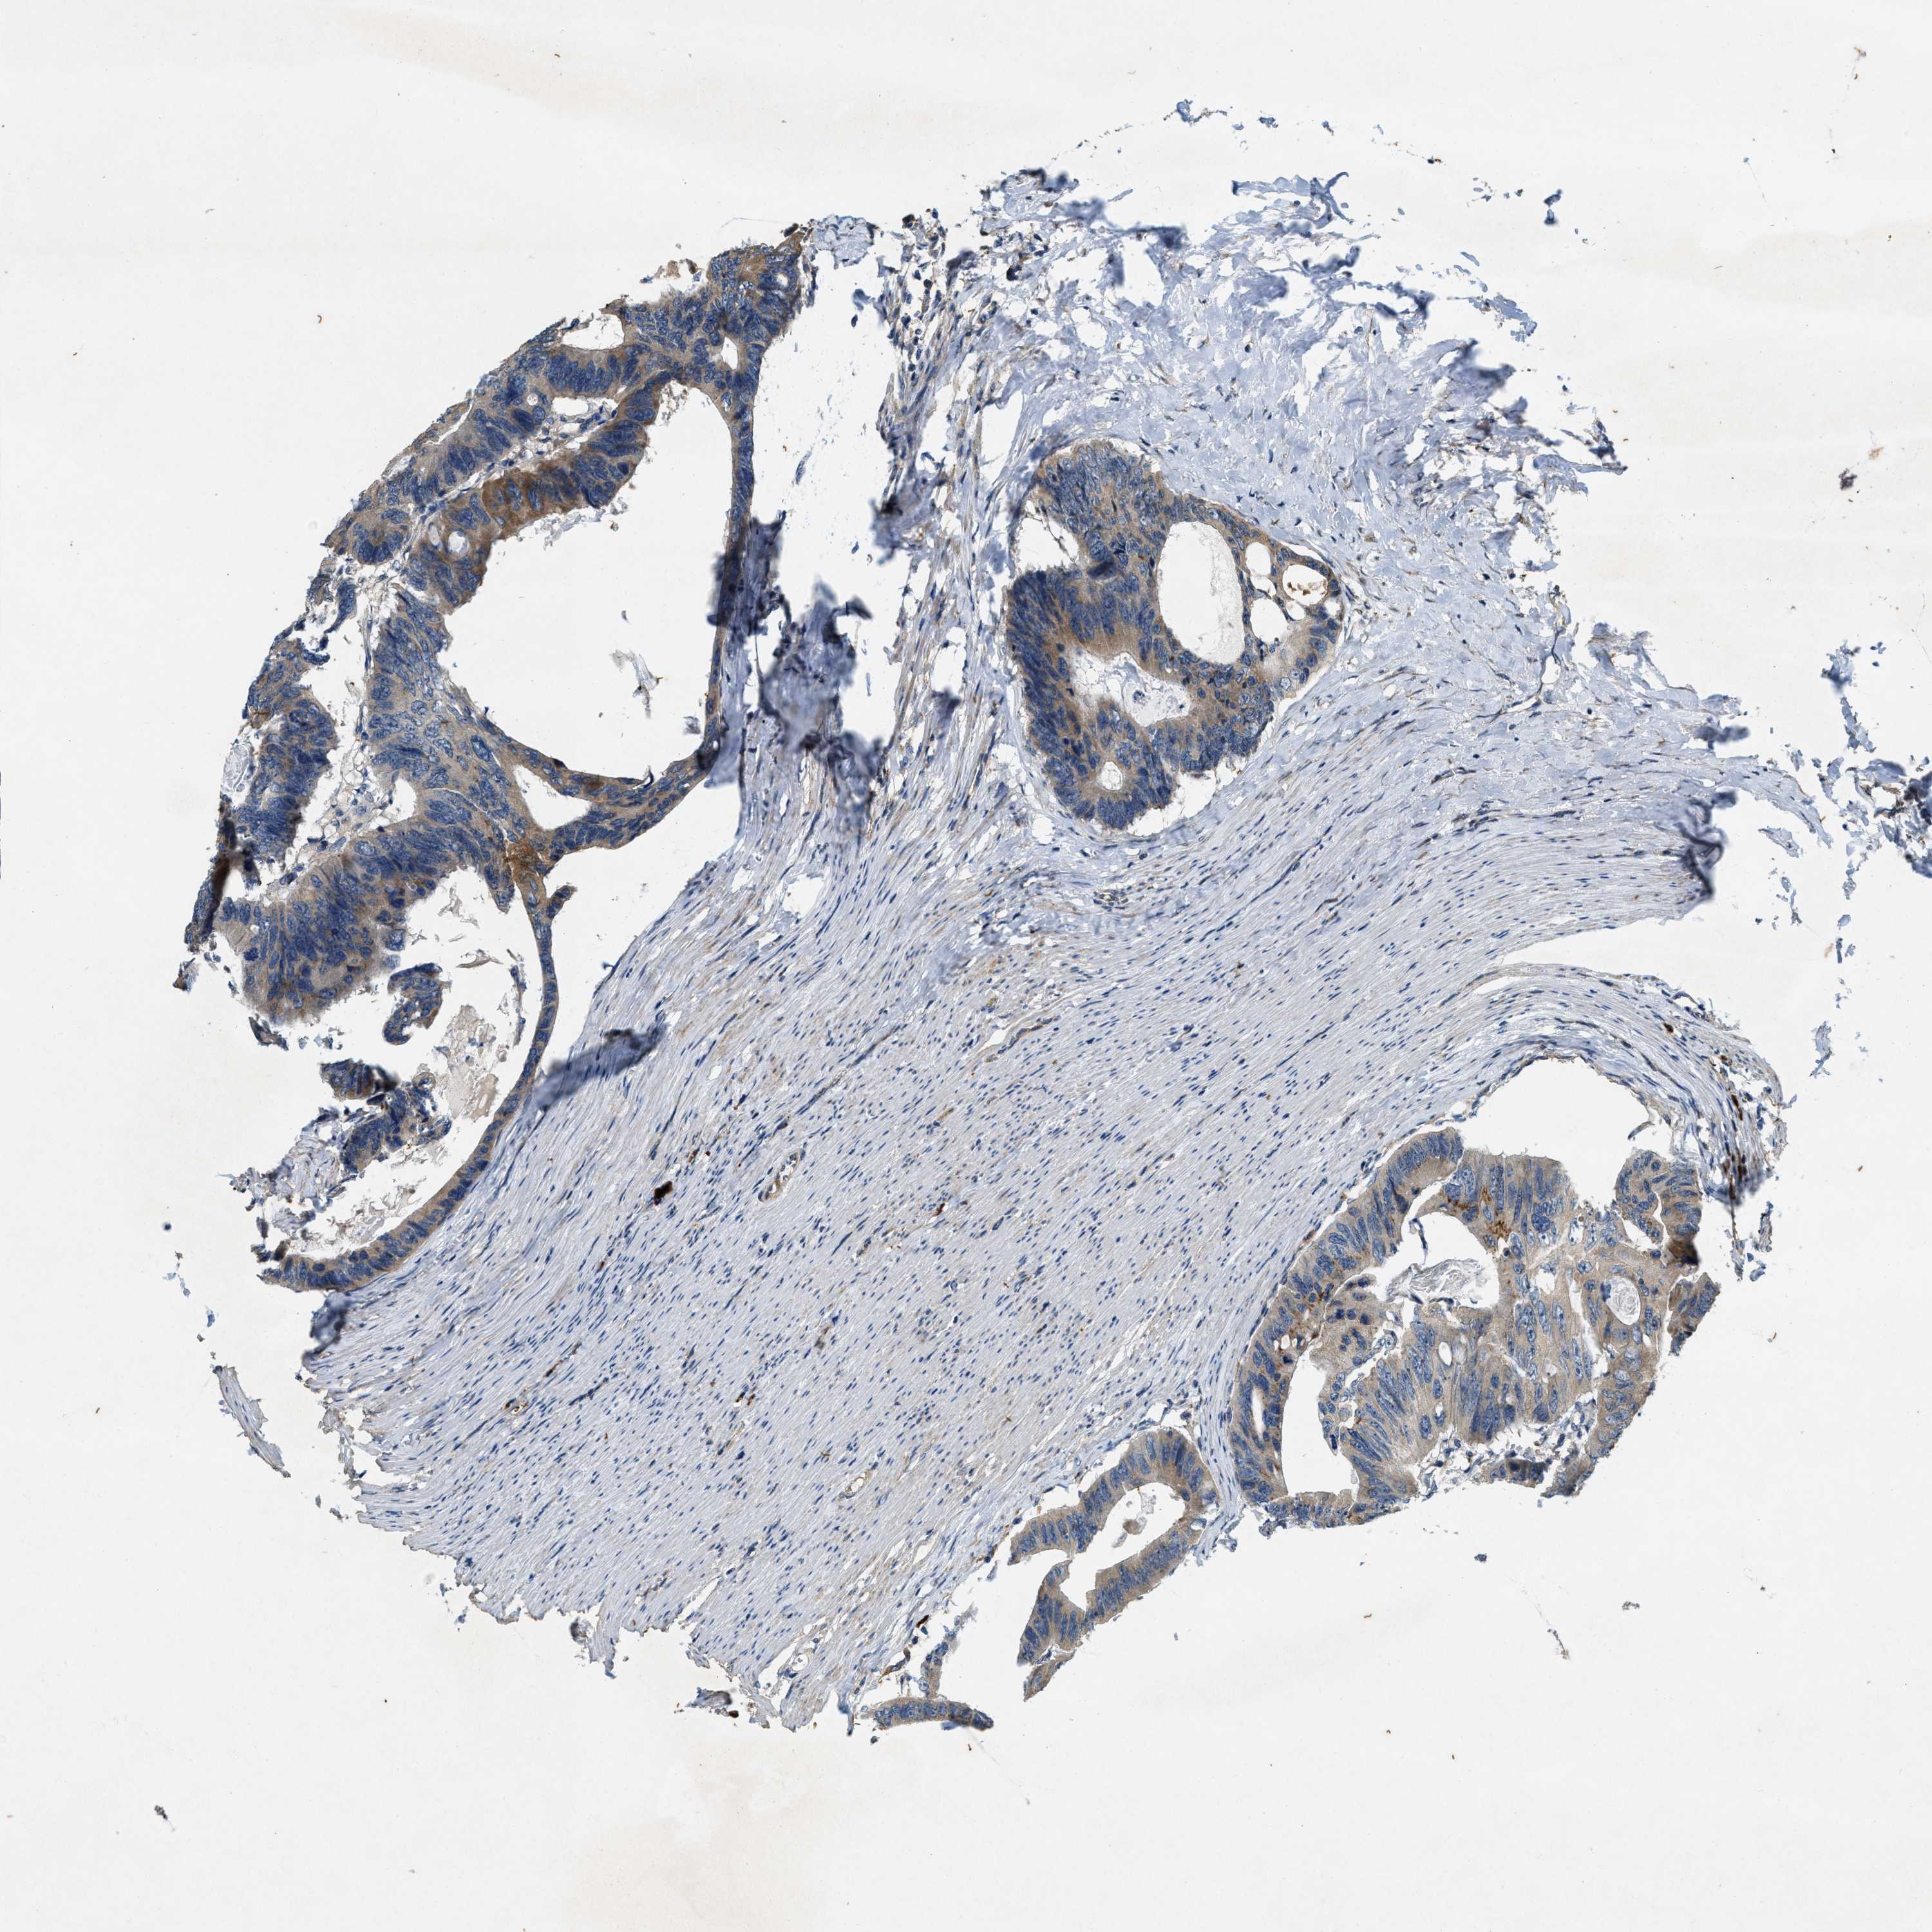

CANCER COLORECTAL CANCER Show tissue menu

Colorectal cancer

Human cancer

Colon adenocarcinoma